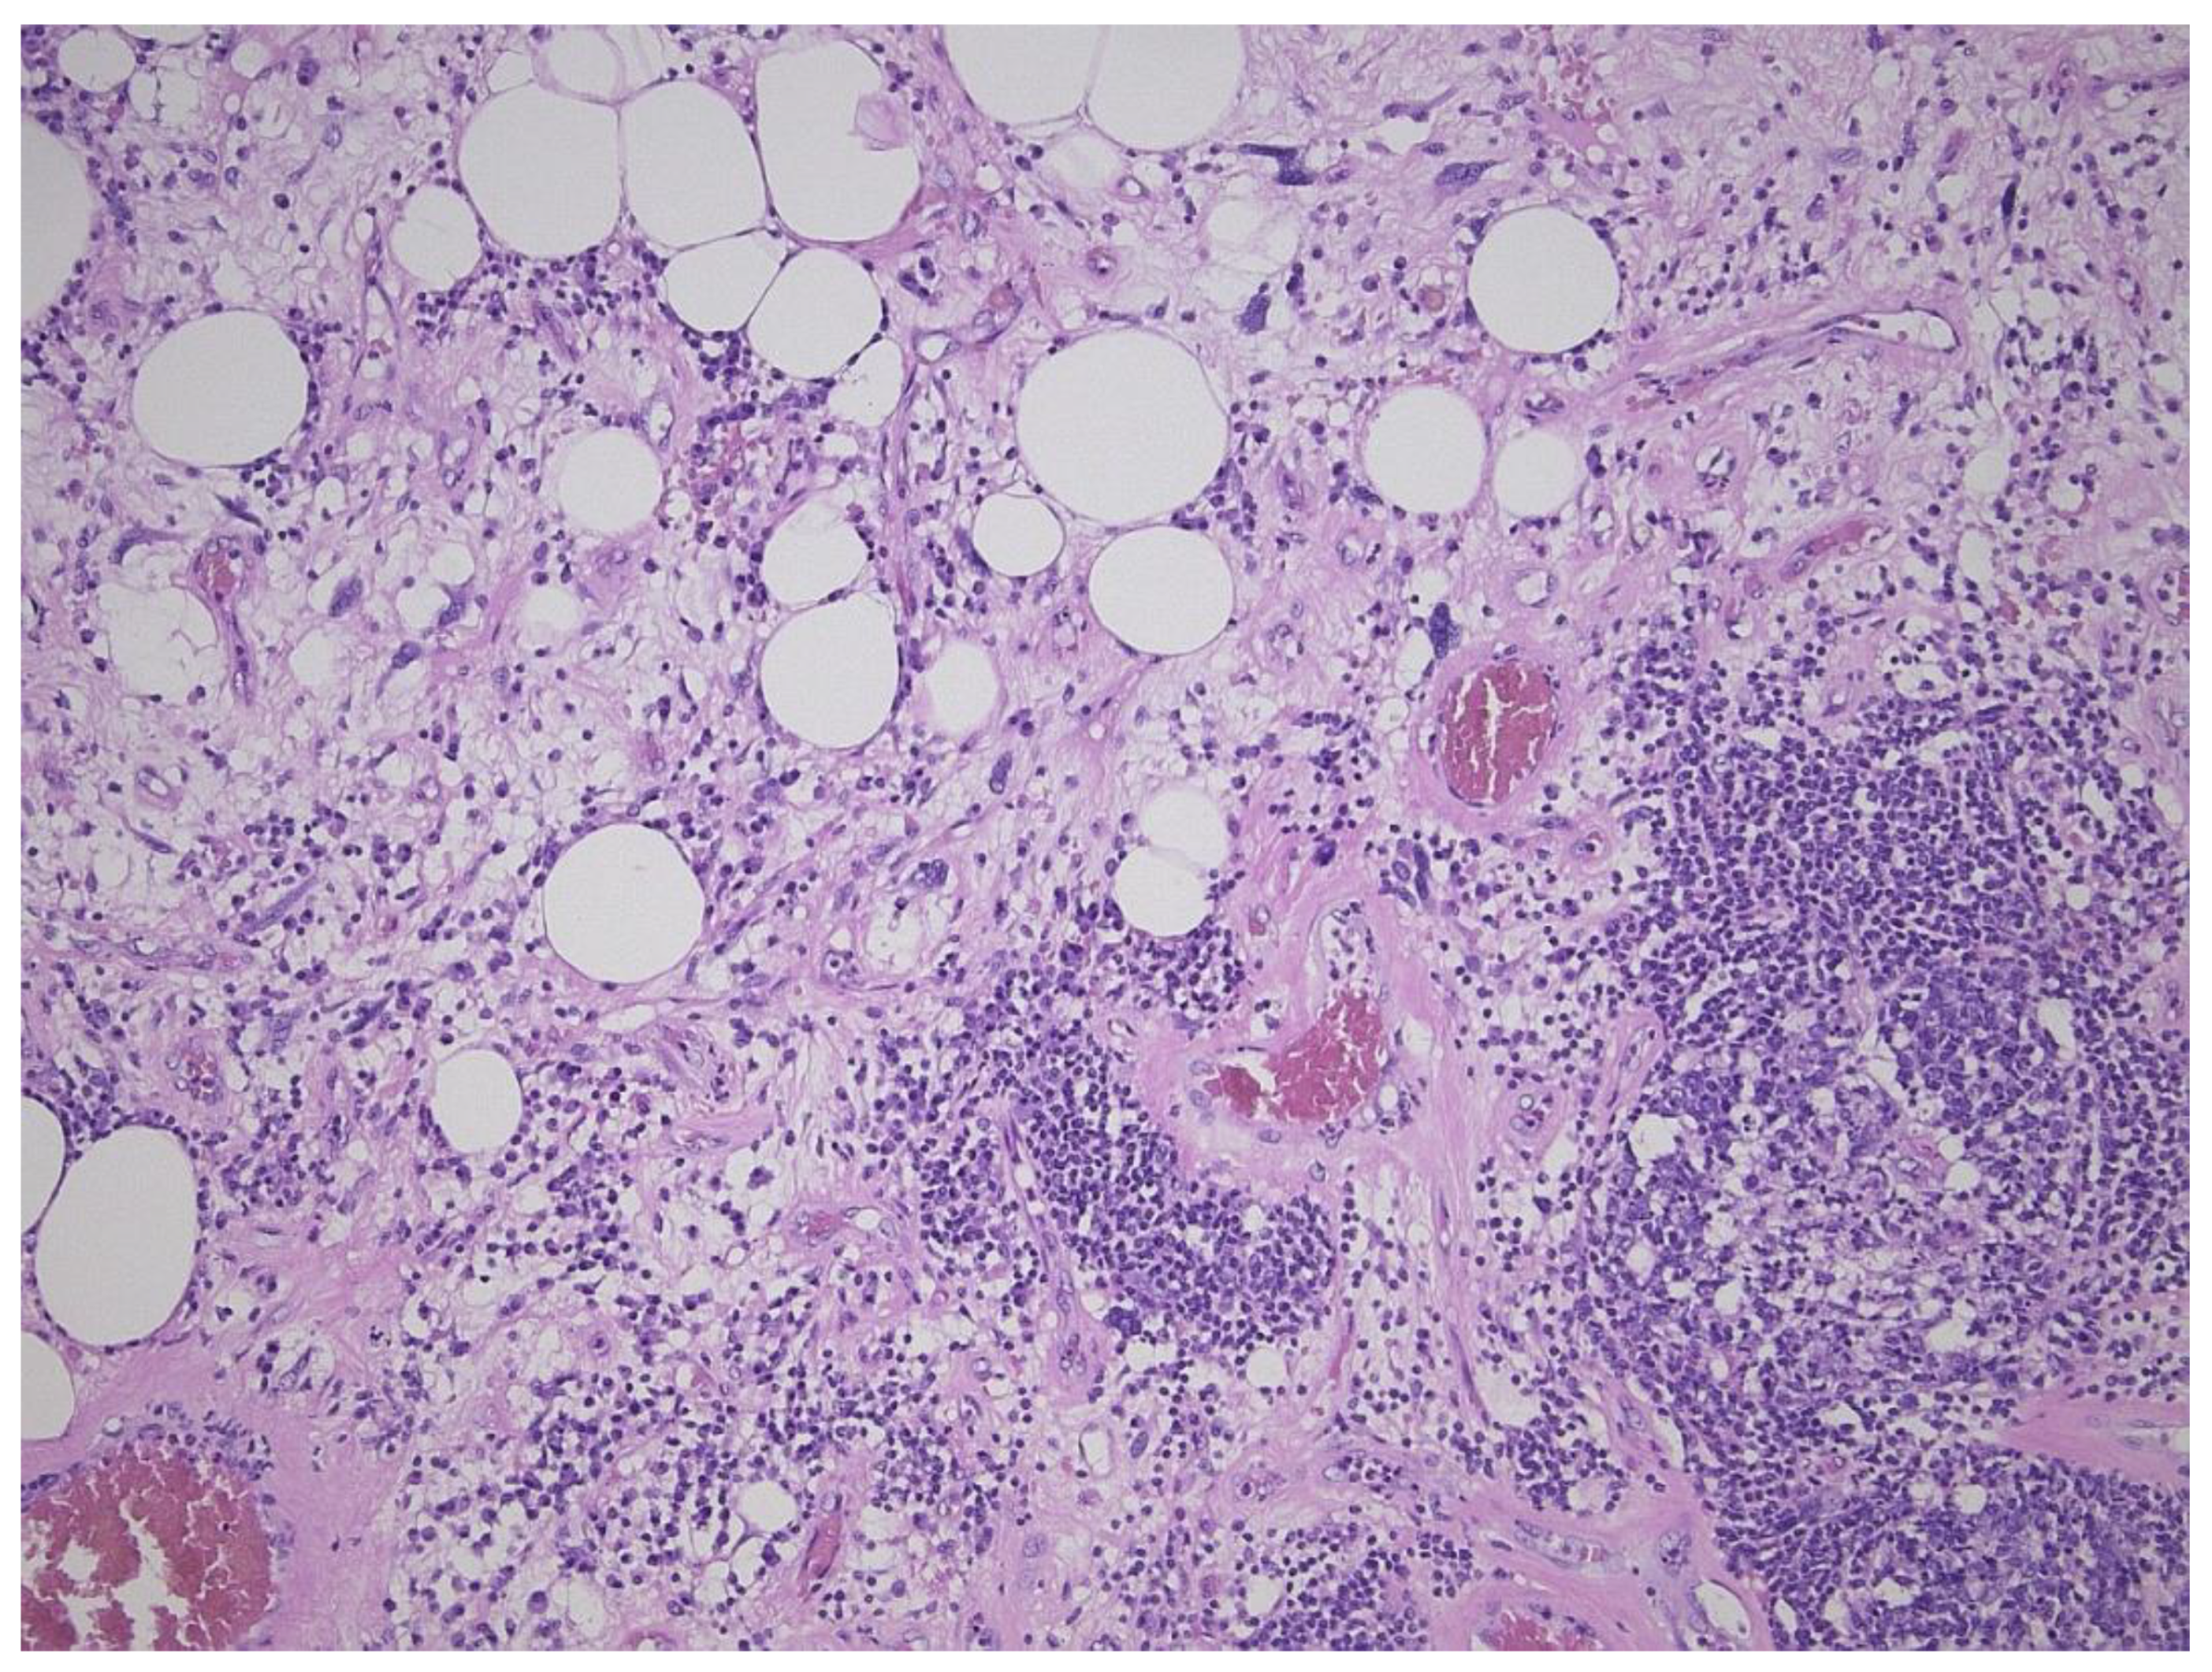

2. Well-Differentiated Liposarcoma/Atypical Lipomatous Tumor (WDL/ATL)